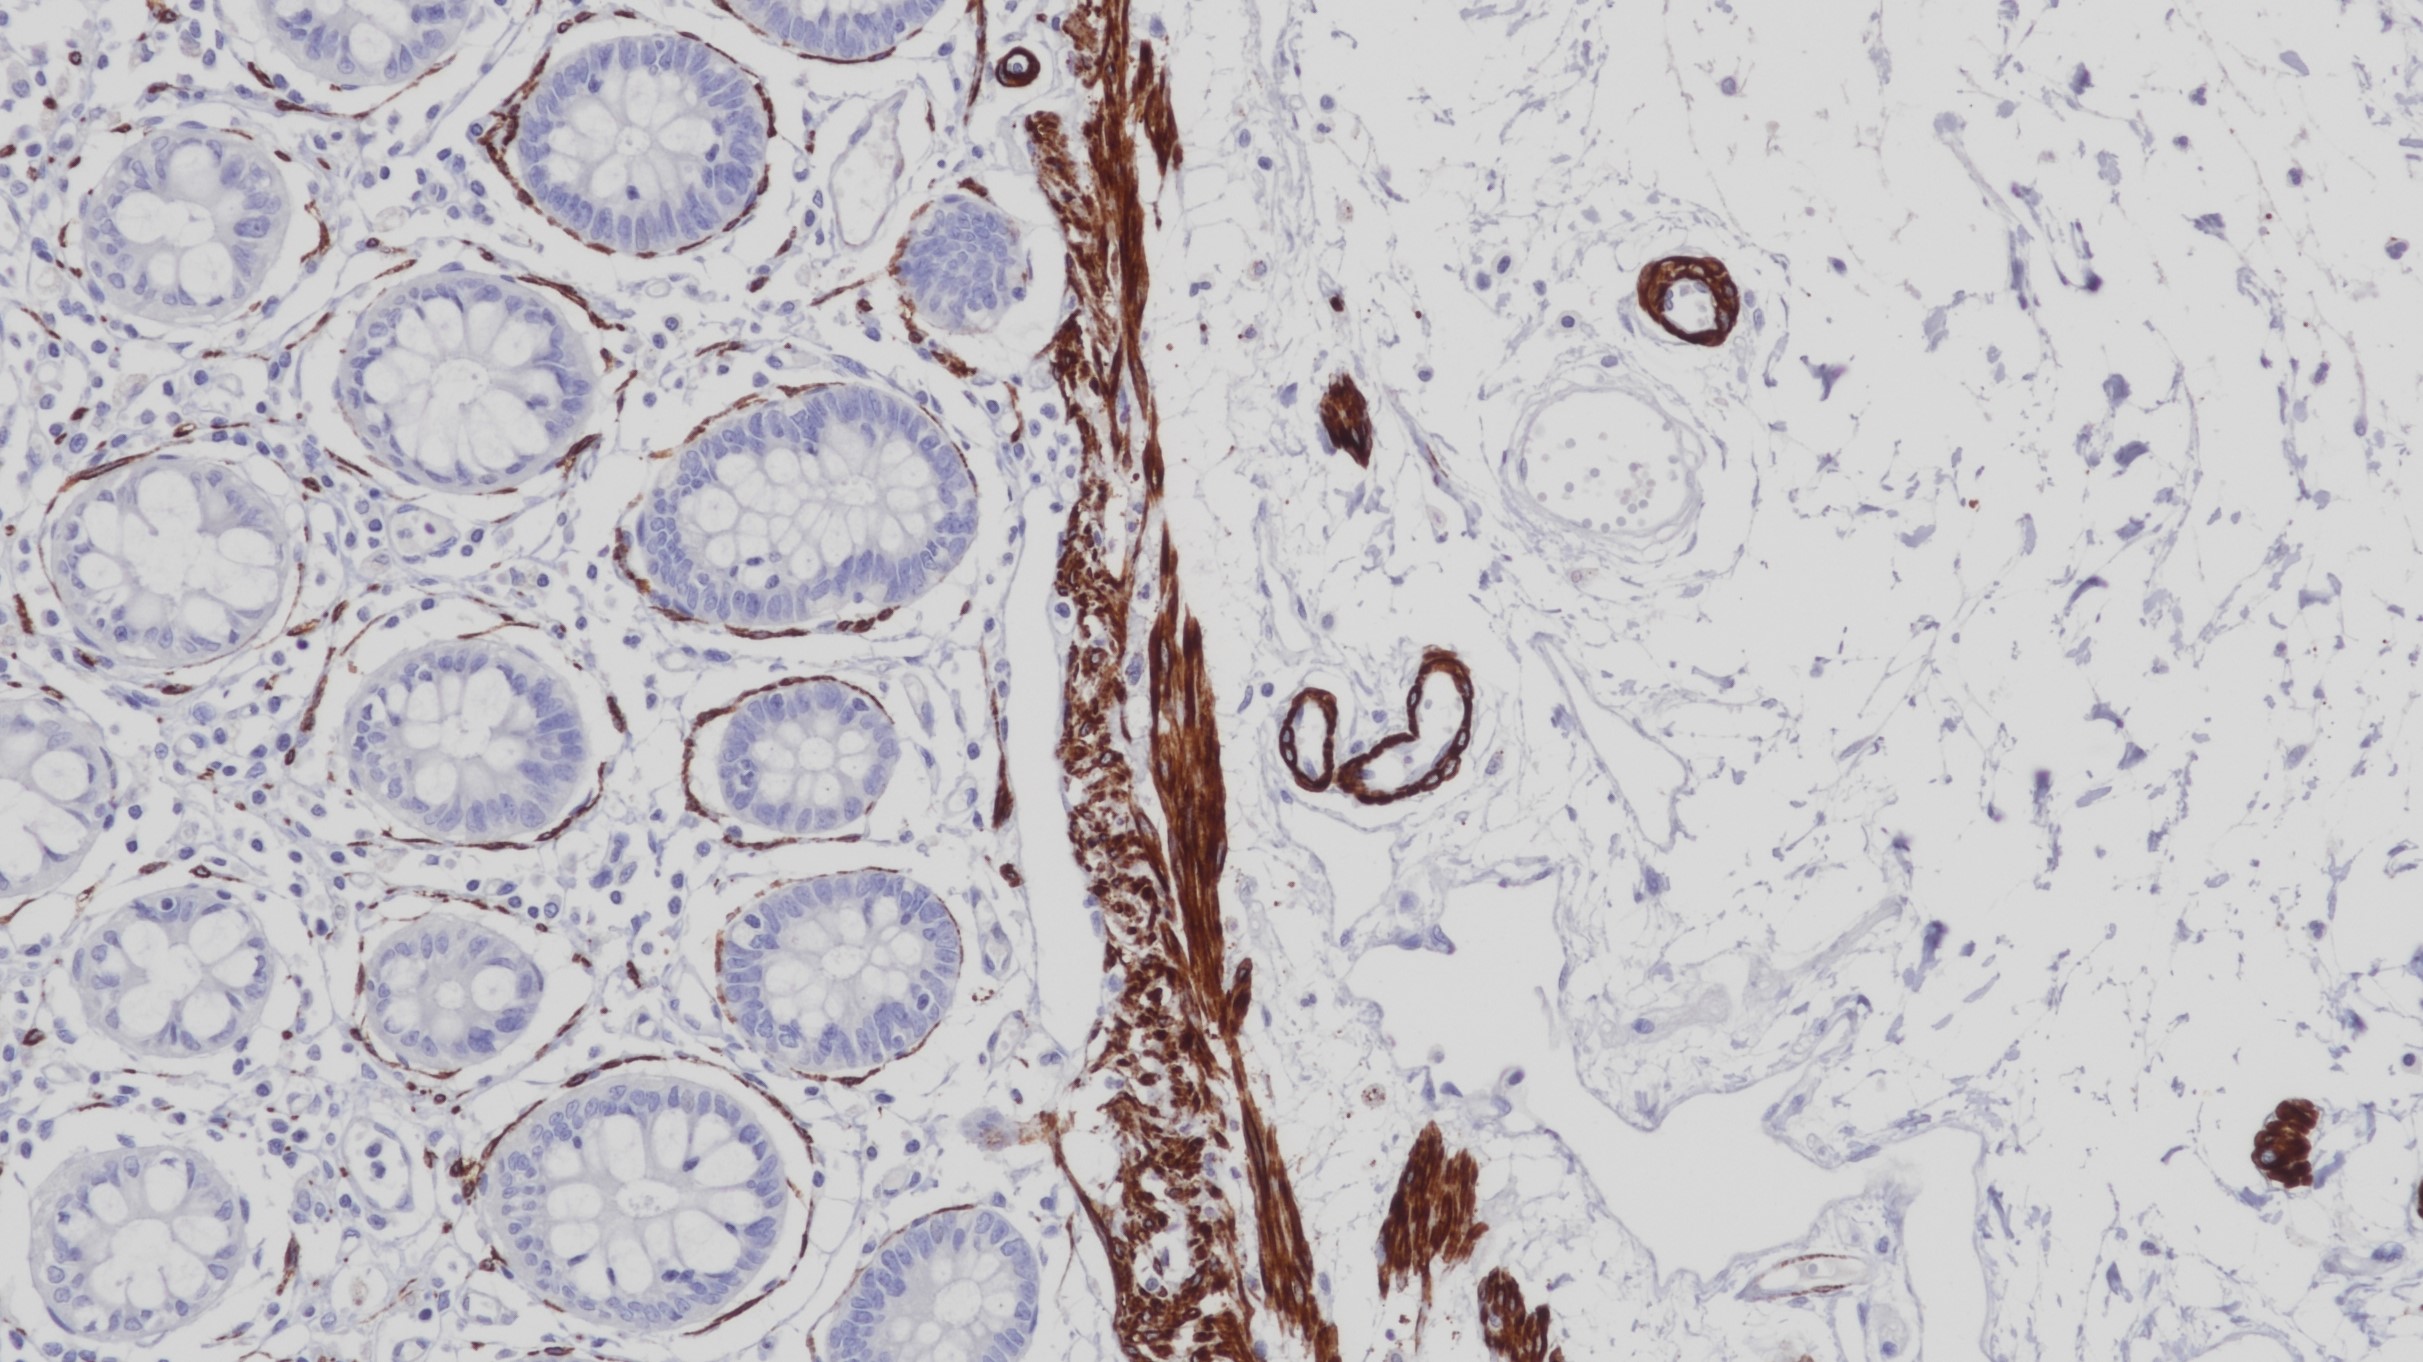

2.Expression and Alpha1-adrenoceptor Regulation of Caldesmon in Human Prostate Smooth Muscle[J] . Sebastian Walther,Frank Strittmatter,Alexander Roosen,Frauke Heinzer,Beata Rutz,Christian G. Stief,Christian Gratzke,Martin Hennenberg. Urology . 2012 (3)